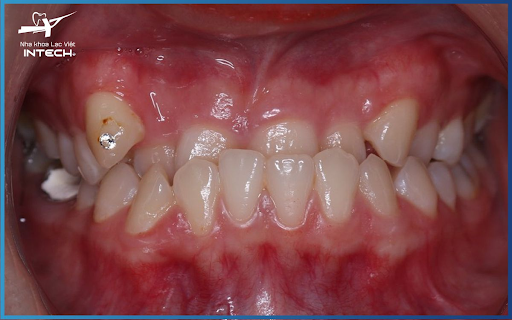

Hô hàm dưới hay còn gọi là răng móm (khớp cắn ngược), là tình trạng răng hàm dưới phủ ra phía ngoài răng hàm trên khi ở trạng thái hai hàm răng cắn chặt. Tình trạng này gây ra các vấn đề về cả thẩm mỹ và chức năng của hàm răng.

Giống như nhiều dạng sai lệch khớp cắn khác, hô hàm dưới của có những dấu hiệu nhận biết riêng:

Hô hàm dưới